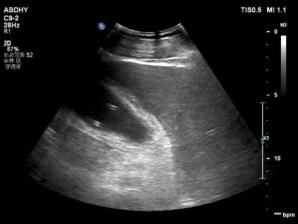

超声科介入室外,患者家属在紧张的等候着,超声介入会诊室内呼吸与重症医学科戚刚强主任、消化科卢王主任、张排旗主任、张蓉主任、外科郭琪医师、超声科黄毅主任在进行会诊。患者老年男性,2月25日收入我院消化科。现患者进行性腹痛4天,高热、寒战并加重2天,(转移性右上腹呈绞痛,墨非氏征阳性,血常规白细胞升高,胆红素升高,糖尿病,注射抗生素效果不佳。)腹部超声检查时超声显示可见胆囊肿大明显,其内液区欠清,胆汁淤积伴脓性细小光点漂浮,有分层,胆囊壁水肿增厚,胆囊颈部可见结石回声,最大径2.2cm,不随体位改变移动。考虑急性化脓性胆囊炎、胆结石嵌顿于胆囊颈。现患者处于急性炎症期,不宜手术切除胆囊,建议先行PTGD术(经皮经肝胆囊穿刺置管引流术)缓解症状,等待情况稳定,炎症控制后,择期手术切除胆囊。